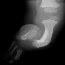

PHYSICAL EXAM: Examination of the right lower extremity demonstrates shortening of the right thigh with a 10 degree flexion contracture present in the knee. The knee is noted to be in valgus. There is moderate anteromedial bowing present in the leg with a dimple present over the anterior aspect of the tibia at the apex of the bow. The foot is held in a position of severe equinovalgus with absence of the lateral two rays noted. There is syndactyly present among the remaining digits. Circulation is normal and skin condition is good. Overall, the right lower extremity is noted to be 5 cm. shortened when compared to the contralateral normal extremity. Attempts at ambulation were limited by the severe deformity present in the right lower extremity.

RADIOGRAPHS: Absent right fibula and lateral two rays of right foot with moderate anteromedial bowing of tibia. The right femur was also noted to be shortened.